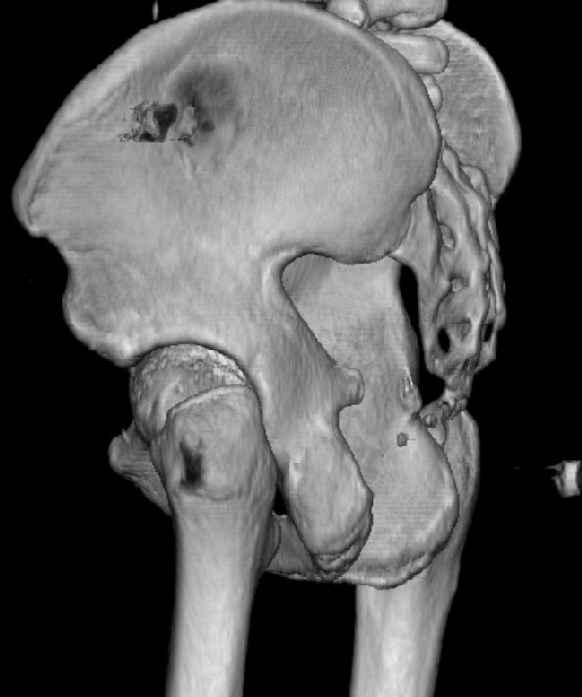

The last two images from the 3-D CT scan certainly makes the fracture look worse than the plan radiographs.

Might have to reconsider my suggestion to leave it alone at this stage.

The joint is non-concentric as the head appears to be either "following the caudal segment", or the dome component is displaced from the tethered head... or so it seems... and he's young... so, many fracture surgeons would recommend reduction and fixation.

So we must decide preoperatively which part is the displaced segment?

It's difficult to know from these few selected images which component of the injury (was before and now) should be deemed the "soon to be mobile"

segment. It's my best guess that it is the caudal portion and there exists a healing fracture line somewhere thru the posterior column...one image

Some more images. Does it help to guess which part of the acetabulum is displaced?

Normal appearing SI joints and a healed posterior column limb... my bet's on caudal segment displacement.